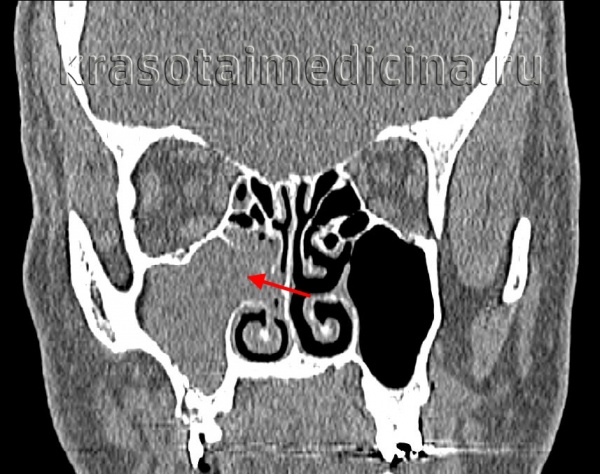

(Слева) При корональной «костной» КТ у девочки 14 лет с муковисцидозом (МВ) определяются типичные признаки ПНП, в т.ч. снижение пневматизации ячеек решетчатой кости справа за счет полиповидного материала, распространяющегося также в полость носа, и доброкачественное ремоделирование костей. Обратите внимание на большое мукоцеле решетчатой кости слева с распространением в орбиту и гипоплазию правой лобной пазухи.

(Справа)При аксиальной «костной» КТ у пациента с МВ визуализируется крупный полип в полости носа справа, связанный со средней носовой раковиной. Выраженная гипоплазия основных пазух часто наблюдается при МВ.